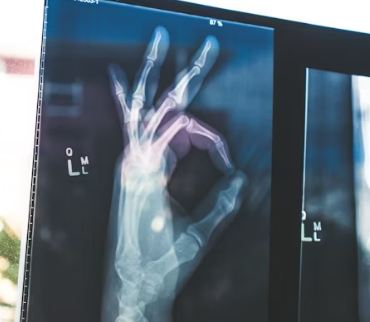

골다공증은 '소리 없는 뼈 도둑'이라는 다른 이름을 가진 질병입니다. 이는 골다공증은 뼈의 밀도가 약해져 작은 충격에도 쉽게 골절되는 질환으로, 특히 40대 이상 여성분들에게 더욱 흔하게 나타나기 때문입니다. 하지만 미리 알고 관리하면 충분히 예방할 수 있습니다.

골다공증은 뼈의 강도가 약해져 골절 위험이 높아지는 질환입니다. 뼈는 한번 만들어지면 끝이 아니라, 평생 동안 오래된 뼈가 파괴되고 새로운 뼈가 생성되는 과정을 반복합니다. 이 과정에서 필요한 영양소가 충분히 공급되지 않으면 뼈 밀도가 점차 감소하게 됩니다.